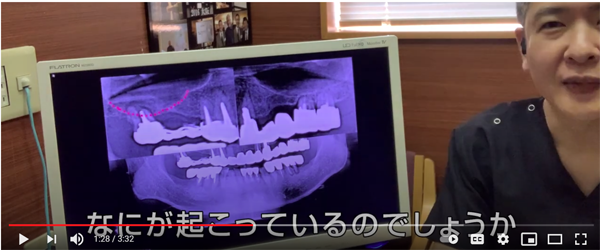

考えただけで

歯がない部分に

ブリッジ治療をしている写真です。

細い歯の方は

歯の根っこが折れました。

こちらは

太い歯

この方は太い歯を土台にした

ブリッジ治療だったので

歯の根っこは折れませんでした

力に耐えられたのですね

ところが

歯を支えている骨

家をイメージすると

柱を支えている地盤

1本1本の柱を支える地盤しか

もともとないわけです。

ブリッジ治療をした場合には

その歯の根っこの周囲の地盤には

本来受ける何倍もの力が実はかかっています。

つまり

地盤沈下が起こってしまうのです